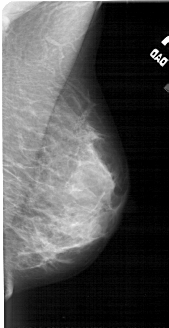

A_1783_1.RIGHT_MLO

RIGHT_MLO LINES 4906 PIXELS_PER_LINE 2521 BITS_PER_PIXEL 12 RESOLUTION 43.5 NON_OVERLAY